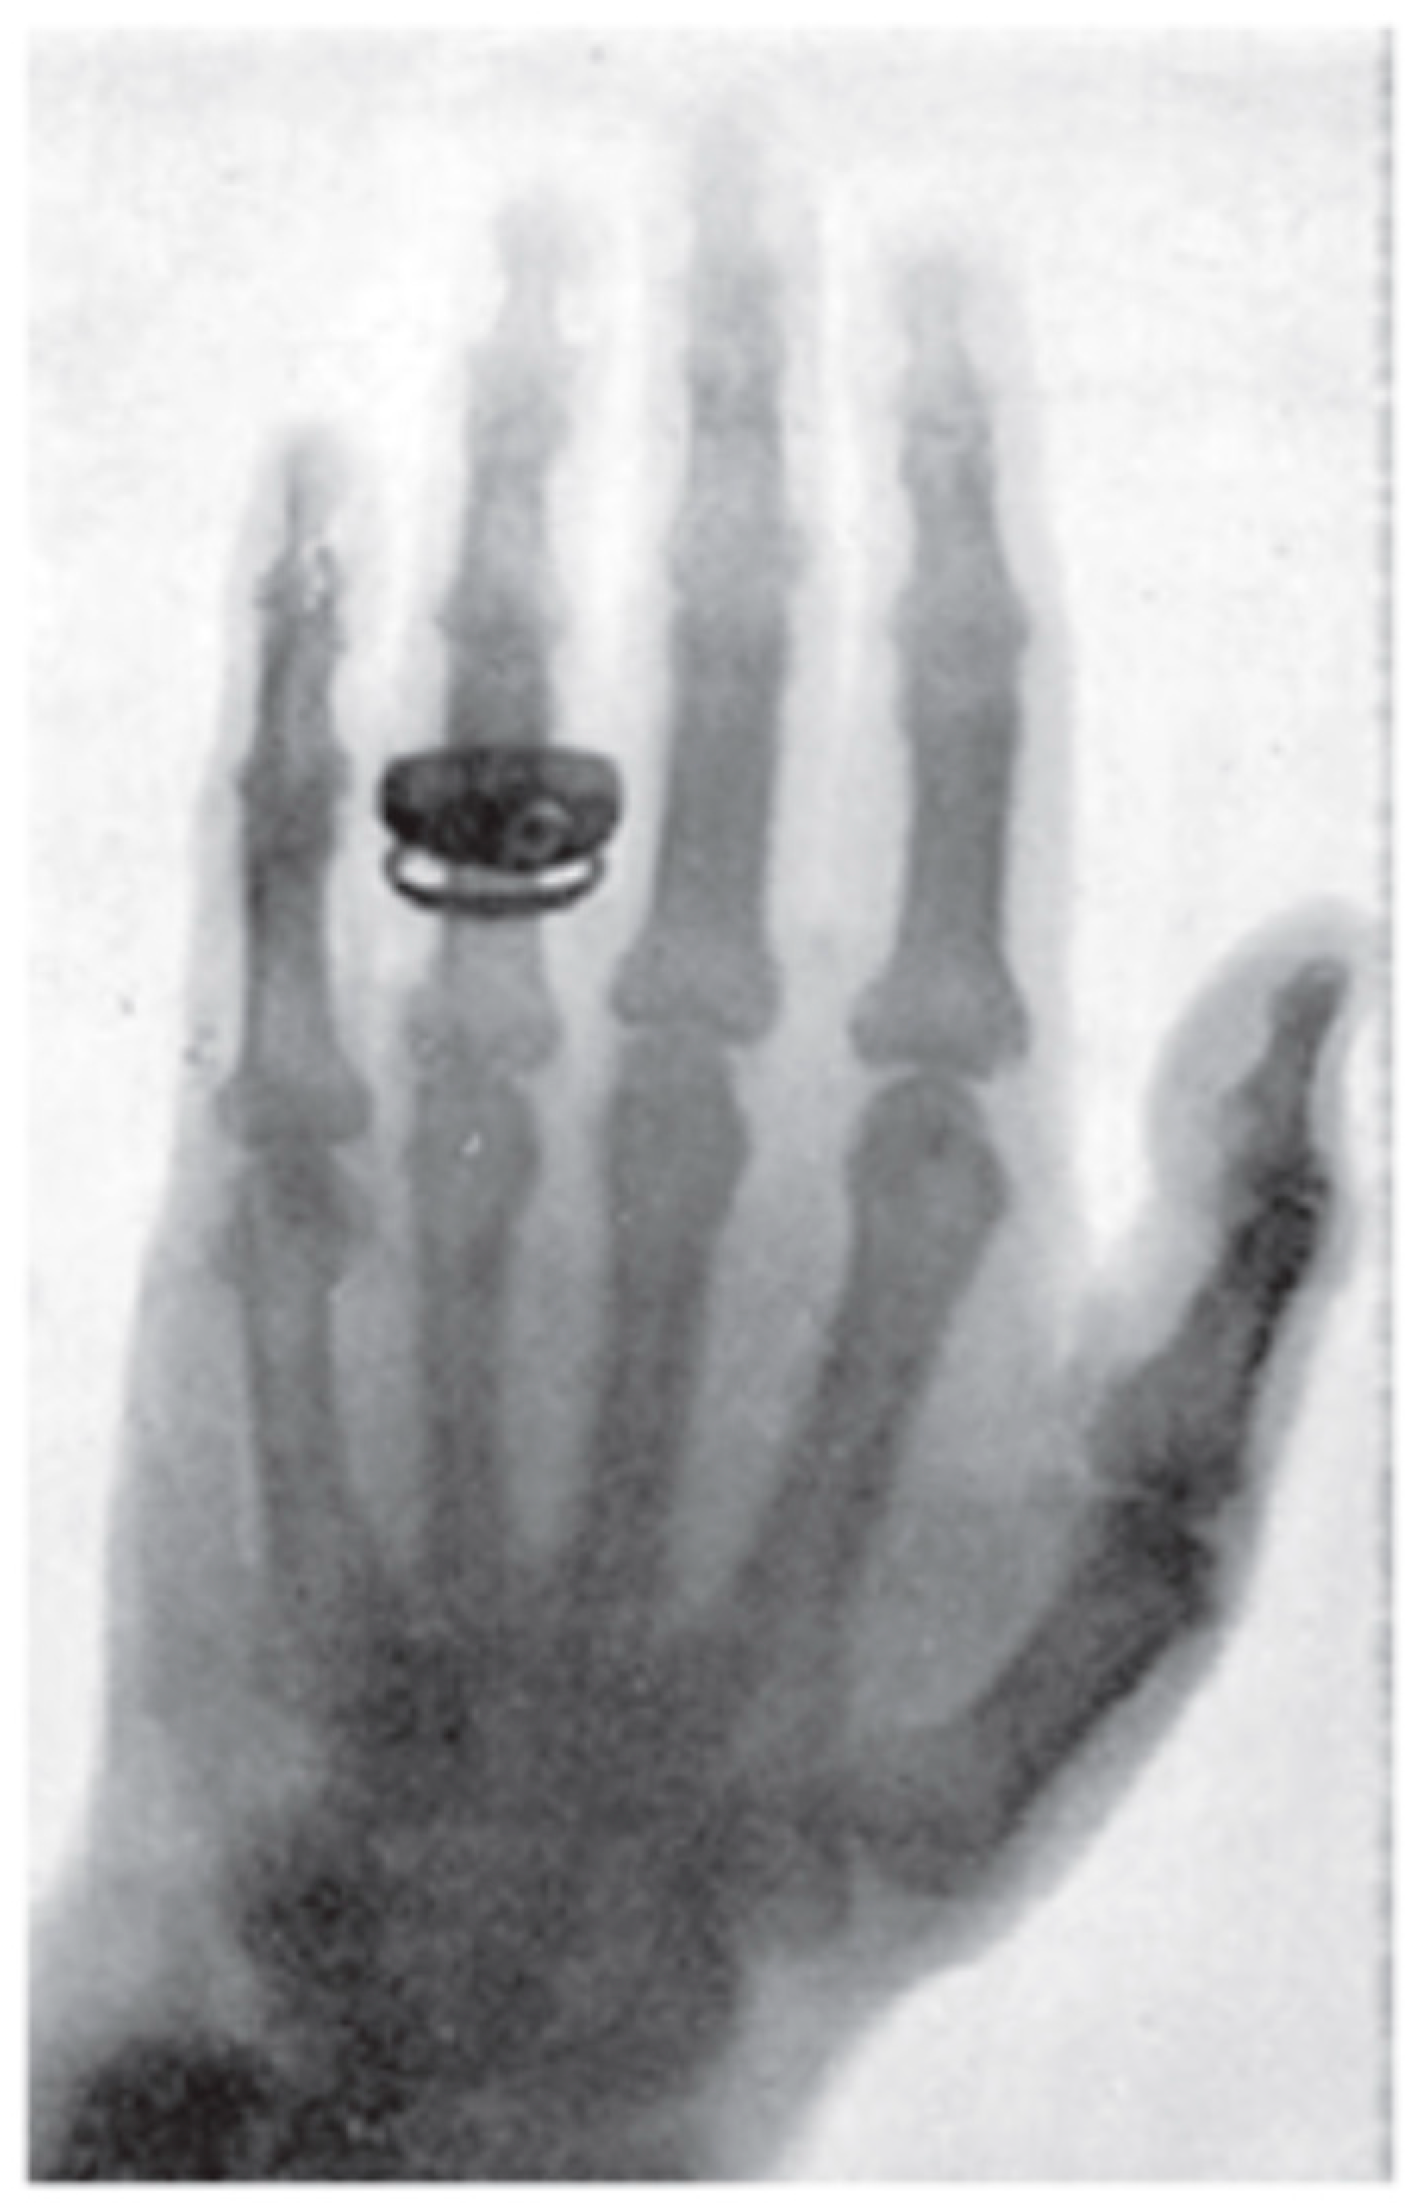

The twenty-eighth of December 1895 is considered as the date of discovery of X-ray, the date on which Roentgen submitted his first “provisorial” communication Uebereineneue Art von Strahlen (On a New Kind of Rays) which was published in the Proceedings of the Würzburg Physico-Medical Society (Sitzungber der WürzburgerPhysik.- MedikGesellschaft). First oral presentation of the discovery was made before the same Würzburg Society on 23 January 1896. The meeting was chaired by the famous anatomist Albert Rudolf von Kolliker (1817–1905) as reported in the Münchener Medicinische Wochenschrift of 29 January 1896. After the lecture Roentgen produced an X-ray picture of Kolliker’s hand in a glass plate (Figure 1). It was Dr. Kolliker who proposed that the new rays henceforth be known as Roentgen rays [4].

Figure 1.

First X-ray picture made in public by Roentgen during his first oral presentation before the Würzburg Physico-Medical Society on 23 January 1896. The picture shows the hand of Albert Kolliker who chaired the talk.